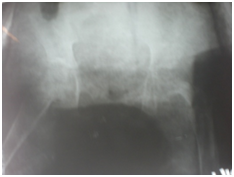

Figure 6 After removal of ex fix and application of Hip Spica cast.

Figure 7 After completion of treatment and removal of hip Spica cast.

Figure 8&9 Compare initial Radiograph and after completion of treatment.